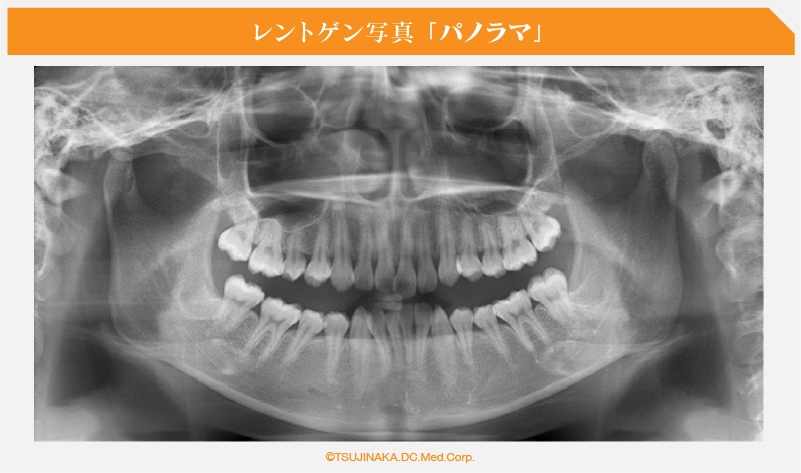

パノラマ「歯並びを横に拡げたレントゲンです」パノラマの写真

埋伏歯の存在、親知らずの存在の有無やその位置や隣の歯との関係、歯周炎の存在、歯の根っこの長さや角度、歯の神経が生きているか死んでいるか、歯が顎の骨と癒着してないか?顎のえらの部分(下顎角)が発達してないか?鼻の空気の通り道が詰まってないか?「鼻中隔湾曲などによる鼻炎」などを診断しています。